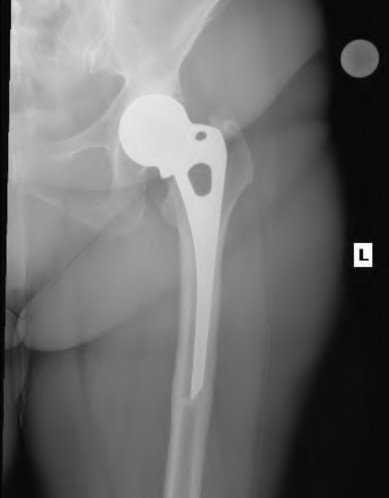

A 72-year-old female presents with progressive left thigh and knee pain for the last year. 5 years ago she sustained a femoral neck fracture treated with the implant seen in Figures A-C (current radiographs). The thigh pain is worse with weight-bearing. C-reactive

protein and erythrocyte sedimentation levels are within defined limits. Which of the following is the most likely cause of her pain?